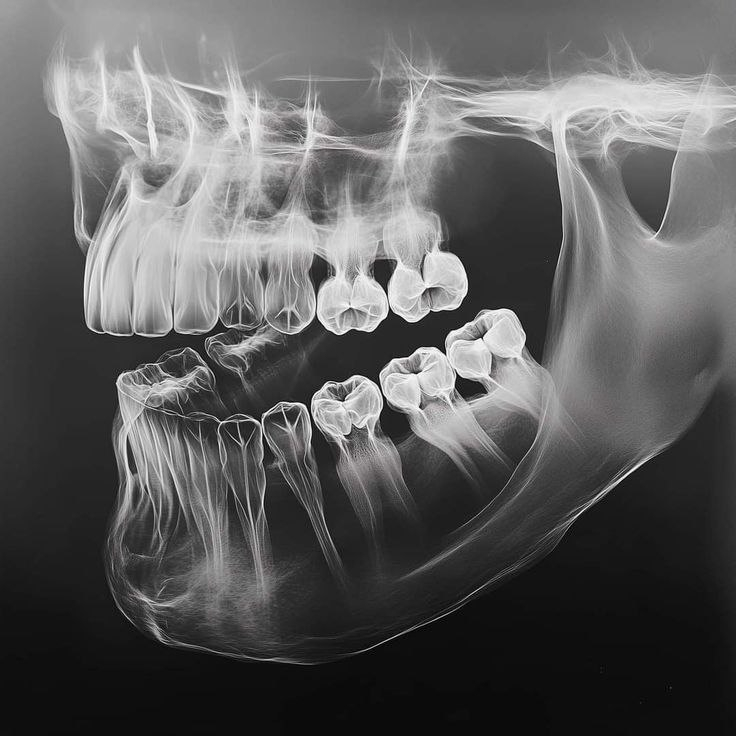

Дентальный снимок — это прицельное двухмерное изображение одного или нескольких зубов. Он используется для выявления кариеса, воспалений, состояния корней и пломб. Такой снимок выполняется быстро, сопровождается минимальной лучевой нагрузкой и широко применяется в повседневной практике.

Компьютерная томография (КТ) позволяет получить трёхмерное изображение зубов и челюстей. Этот метод даёт более детальную информацию о костной ткани, положении корней, скрытых патологиях и анатомических особенностях. КТ чаще назначают при имплантации, сложном лечении и планировании хирургических вмешательств.